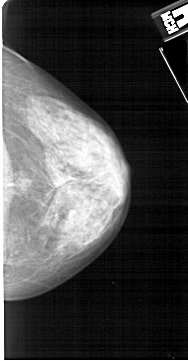

A_1338_1.RIGHT_MLO

RIGHT_CC LINES 5041 PIXELS_PER_LINE 2626 BITS_PER_PIXEL 12 RESOLUTION 43.5 NON_OVERLAY

RIGHT_MLO LINES 5491 PIXELS_PER_LINE 2746 BITS_PER_PIXEL 12 RESOLUTION 43.5 NON_OVERLAY